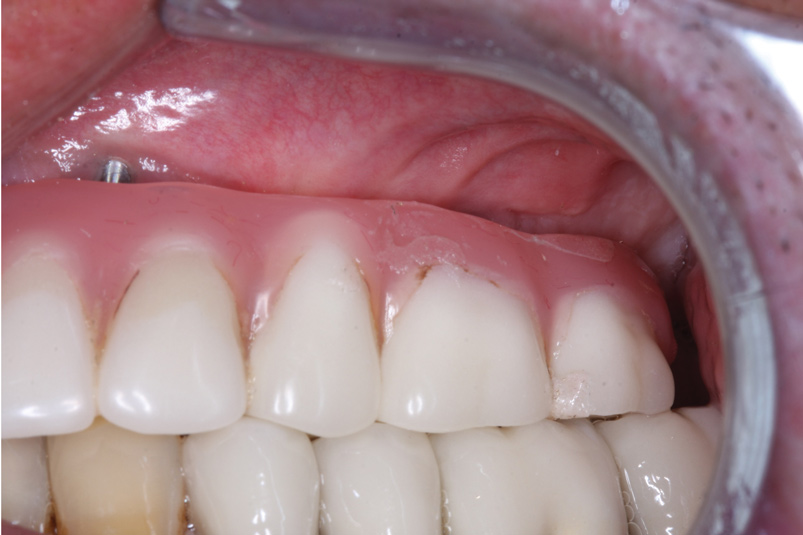

The patient returned in August 2016, when the maxillary prosthesis and healing abutment were removed. A LOCATOR F-Tx abutment was placed into the implant at No. 13 (Figure 5).

The existing prosthesis framework was then modified, and the system denture attachment housing was luted to the framework using a chairside acrylic material (Figure 6). The underside of the prosthesis was cleaned, adjusted, and polished (Figure 7). The prosthesis was delivered using a medium PEEK retention ball (tan) to secure the prosthesis at this site, snapping into the abutment; the remainder of the prosthesis continued to be retained by prosthetic screws in the sites with screw-retained abutments (Figure 8). A postoperative radiograph confirmed osseointegration (Figure 9), and a left-lateral close-up view illustrated the ideal esthetics and fit achieved with the LOCATOR F-Tx fixed attachment. (Figure 10).

Fig 5. A spherical 4-mm fixed LOCATOR F-Tx abutment was placed into the implant at No. 13.

Figure 5

Fig 10. Left-lateral close-up view illustrating the ideal esthetics and fit achieved with the LOCATOR F-Tx attachment.

Figure 10